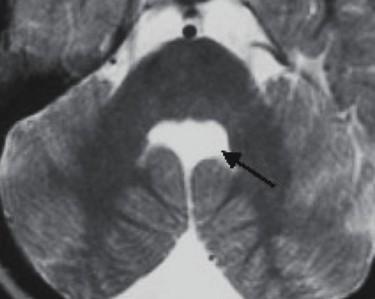

Fused hemispheres, absent or hypoplastic vermis, and superior cerebellar peduncles

Needs to have fusion of the dentate nuclei

Assn: hydrocephalus, limbic anomalies, cortical malformations, absent septum pellucidum, multiples suture synostosis

Where is the vermis? Big or small?

Do you have a normal fastigial point?

What is the abnormal horizontally oriented structure? What is the diagnosis?

Where is the vermis? Big or small? Too small…

Do you have a normal fastigial point? Yes, pointed… What is the abnormal horizontally oriented structure? the superior cerebellar peducle…

What is the diagnosis?

What is the yellow arrow pointing to?

“molar tooth” midbrain

Large horizontally oriented superior cerebellar peduncles

Small, dysplastic vermis

“bat wing” 4th ventricle configuration

Associated with:

Absence of decussation of WM pathways in brain stem on DTI

Supratentorial:

Absent septum pellucidum

Fused fornices

Ventriculomegaly

Polymicrogyria

White arrows: Small pons remnant with nonformation of the midportion of the brainstem

Clinical: cranial neuropathies

Associated with small cerebellum

Abnormal vertebrobasilar vasculature

Etiology?

very early vascular insult?

No gliosis to suggest hypoxia or ischemia

In animals: seen with hox gene deletions leading to lack of single rhombomere development, so brainstem “short” but typically not fully disconnected